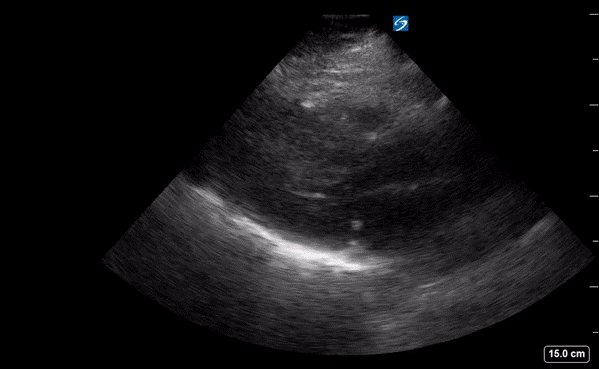

A point-of-care ultrasound was performed to evaluate for potential etiologies of syncope. The ultrasound displayed biventricular and interventricular septal hypertrophy (Figure 2), systolic anterior motion of the mitral valve (SAM, Figure 3), and a “dagger-like” continuous wave Doppler waveform emerging from the left ventricular outflow tract. (LVOT, Figure 4)

Figure 2. Parasternal long-axis view displaying a hypertrophic left ventricle (LV) and right ventricle (RV).